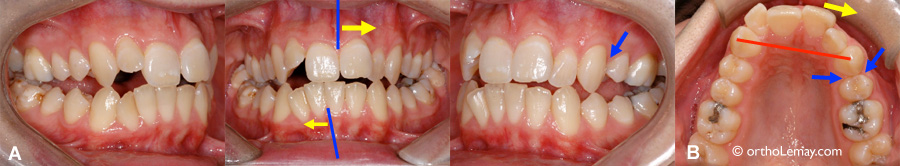

Malocclusion sévère (béance antérieure et postérieure, constriction maxillaire, chevauchement dentaire, asymétrie). Une prémolaire supérieure gauche fut extraite en bas âge (flèches bleues), les dents supérieures ont dévié de ce côté, exacerbant l’asymétrie de la ligne médiane (A et B – flèches jaunes et ligne rouge), n’améliorant aucunement la sévérité de la malocclusion, l’esthétique ou la fonction. Ce cas requiert toujours une intervention orthodontique majeure, mais l’orthodontiste doit en plus composer avec une asymétrie plus importante.